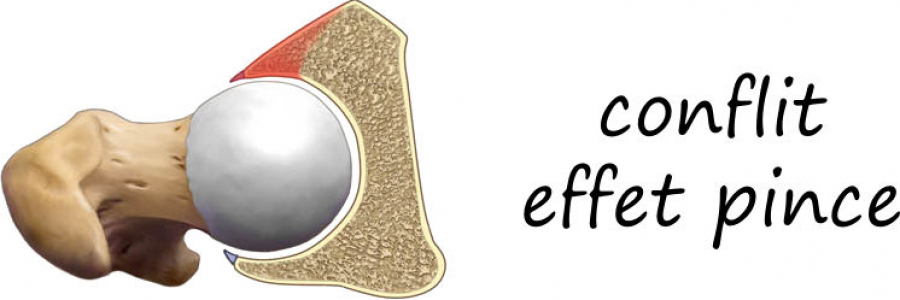

Classiquement il existe 3 formes possibles de conflits fémoro acétabulaires:

- par effet pince : le facteur prédominant est une couverture antérieure excessive du cotyle qui vient appuyer sur le col en flexion

Il s’y associe presque systématiquement toujours une déchirure du bourrelet cotyloidien (labrum tear).